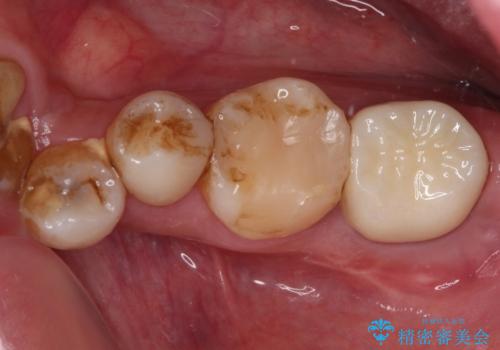

放置した虫歯 根管治療とオールセラミッククラウン

- 奥歯の虫歯を放置してしまい、痛みを感じることがあるとのことで来院された患者様です。

術前の診査では、神経を取り除かなくても済む可能性が示唆されましたが、実際に虫歯除去を進めたところ、レントゲン写真から読み取れる通り、神経組織にまで虫歯が及んでいることが分かりました。

速やかにラバーダム下にて根管治療を行うこととし、その後オールセラミッククラウンにて補綴治療を行うこととしました。